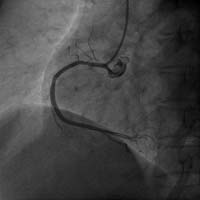

右冠状动脉闭塞 介入术后右冠开通